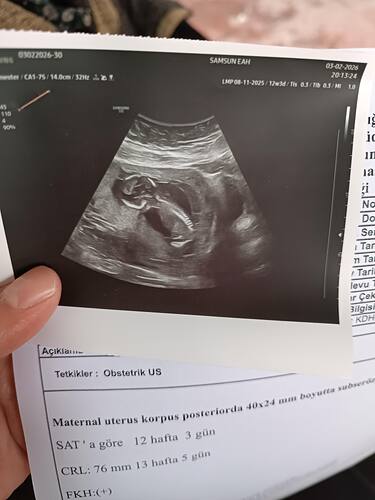

Daha çok küçük değilmi tahmin için

Evet ama bazen keseye görede tahmin yapabiliyorlar ya merak benimki

Kese yuvarlak bence kız erkek olsaydı fasulye gibi şekilli olurdu benim oglumda doktor 6 haftalıkken senin olgun olur fasulyen var demişti buda Kısmet aetık

Hayır canım fark etmemiştim seninkini ama kese şekline bakılırsa erkeğe benziyor seninki benim bebişin de kese benzerdi erkek bebek bekliyoruz![]()